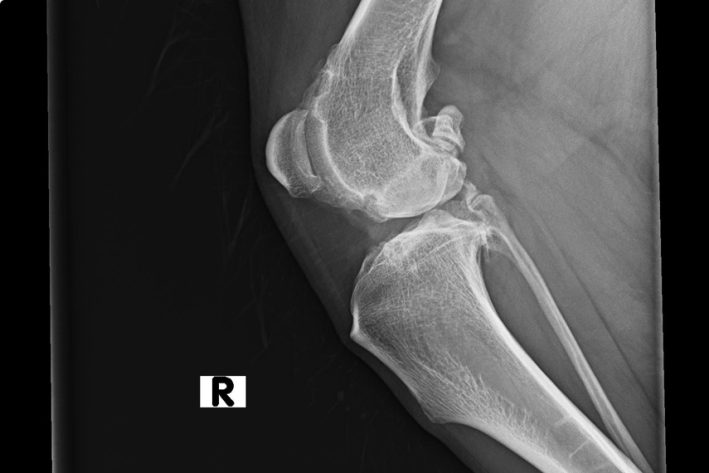

Röntgenbild Hochgradige Kniegelenksarthrose

Hochgradige Kniegelenksarthrose sekundär zu einer chronischen OCD Läsion